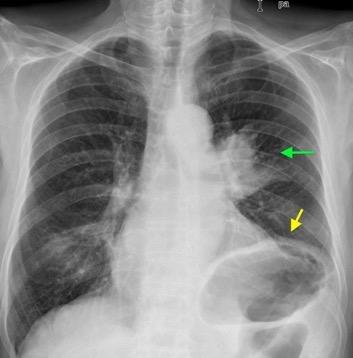

Tromboembolismo pulmonar Diafragma elevado 20%

Nódulos pulmonares múltiples. (flechas verdes). Masas paratraqueales. (flechas amarillas). Dudoso ensanchamiento retrocrural (flechas negras). sigue….

T. mixto de células germinales del testículo

izquierdo Metástasis pulmonares. (flechas verdes). Ganglios paratraqueales. (flechas amarillas). Ganglios retroperitoneales (flechas negras)